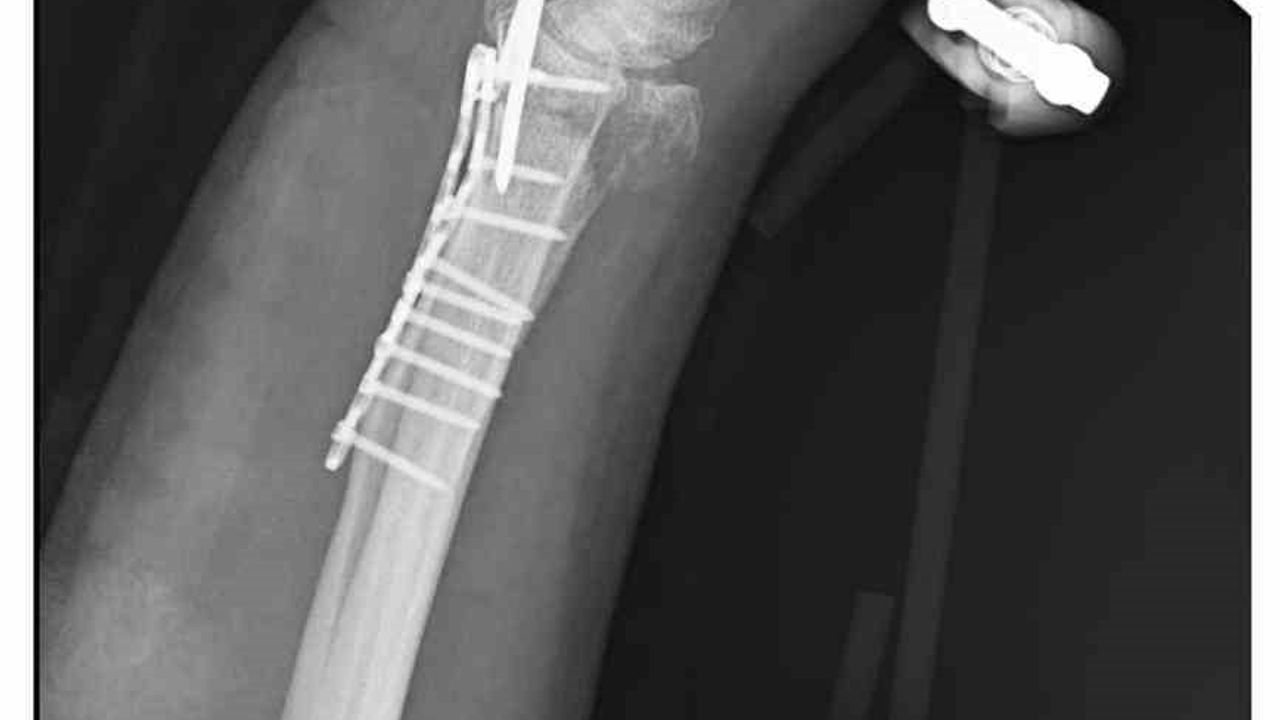

Ankara'nın Mamak ilçesinde, 29 Aralık günü meydana gelen olayda 35 yaşındaki Yasin Arslantaş, yaşadığı apartmanın önünde karşılaştığı sahipsiz köpeklerden kaçmaya çalışırken ayağının kayması sonucu düştü ve el bileği kırıldı. Olay sonrası ambulansla hastaneye kaldırılan Arslantaş'ın bilek kemiğine 11 adet platin yerleştirildi.

Arslantaş, olay anını şöyle anlattı: 'Sabah apartmandan çıkarken arkamdan 9 köpeğin geldiğini gördüm. Saldırganlardı. Kaçmaya çalışırken düştüm.' Yaralanma sonucu bileğinde 15 dikiş olduğunu, geçirdiği ameliyatın 3 saat sürdüğünü ve kolunda kalıcı his ile hareket kaybı olabileceğinin kendisine bildirildiğini söyledi.